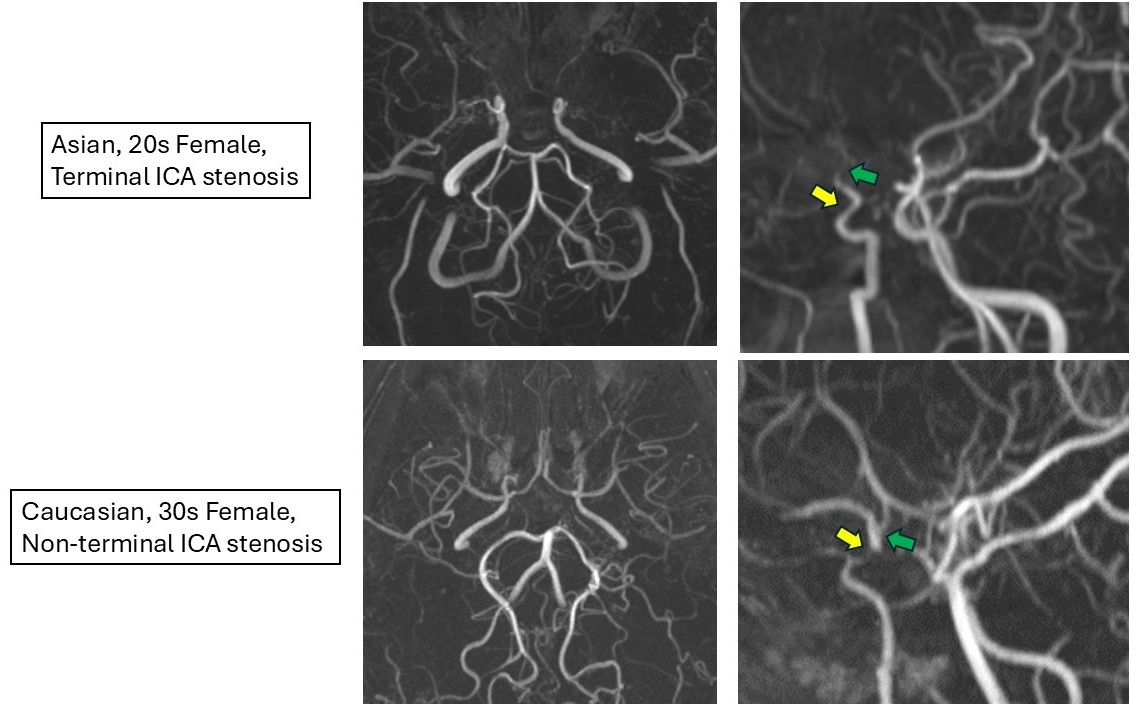

Detailed demographic and clinical characteristics of 107 patients evaluated were listed in Table 1. By reviewing MRA, we have identified a subset of patients with unique imaging features characterized by ICA stenosis localized proximal to the terminal portion of ICA, differing from the typical lesion sites seen in MMD (Fig. 2). This non-terminal ICA stenosis was more frequently observed in Caucasian than in Asian patients (17.5% vs. 5.7%, P=0.007). Compared to patients with terminal ICA and/or MCA stenosis, patients with non-terminal ICA stenosis were older (P=0.03), had less advanced disease stages (P<0.001), and displayed fewer basal moyamoya collaterals (P=0.002).

Using the imaging-based approach of vascular structural features, we have identified a potential subtype of moyamoya disease characterized by non-terminal ICA stenosis. This subtype may have a different pathophysiology from patients with typical ICA terminal stenosis, potentially driven by distinct genetic and epigenetic factors. Ongoing investigations are focused on elucidating these factors and their implications in MMD.